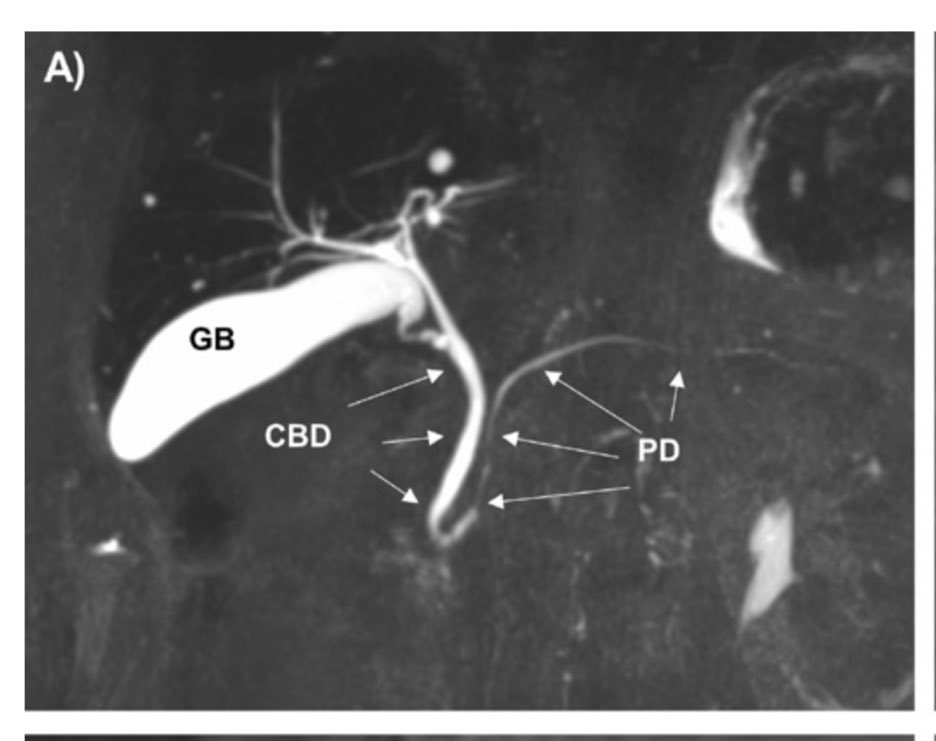

Setting the standards 📐 of common bile duct and pancreatic duct 🌱 CBD up to 8 mm < 65 y/o and up to 11 mm in ≥65 y/o 🍡 PD diameters up to 3 mm in <65 y/o and up to 4 mm in ≥65 y/o Landmark open access @Gut_BMJ paper 👏 kudos to authors ! 👉 https://t.co/hGEkfeVeRc